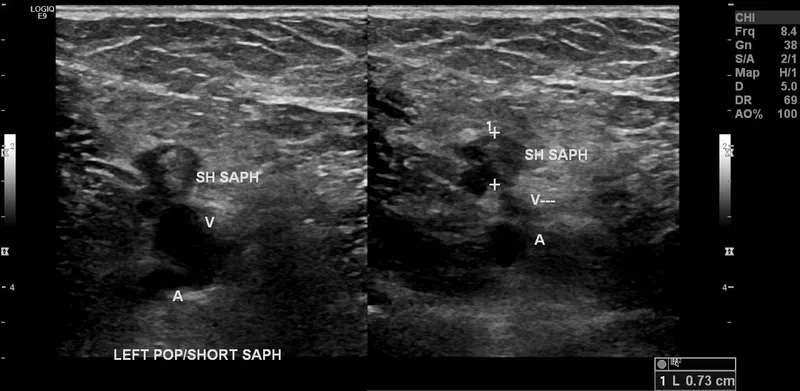

- First-line Imaging: Compression ultrasonography with Doppler. Shows non-compressible vein.

- Diagnose DVT with duplex ultrasound; diagnose PE with CT angiography.